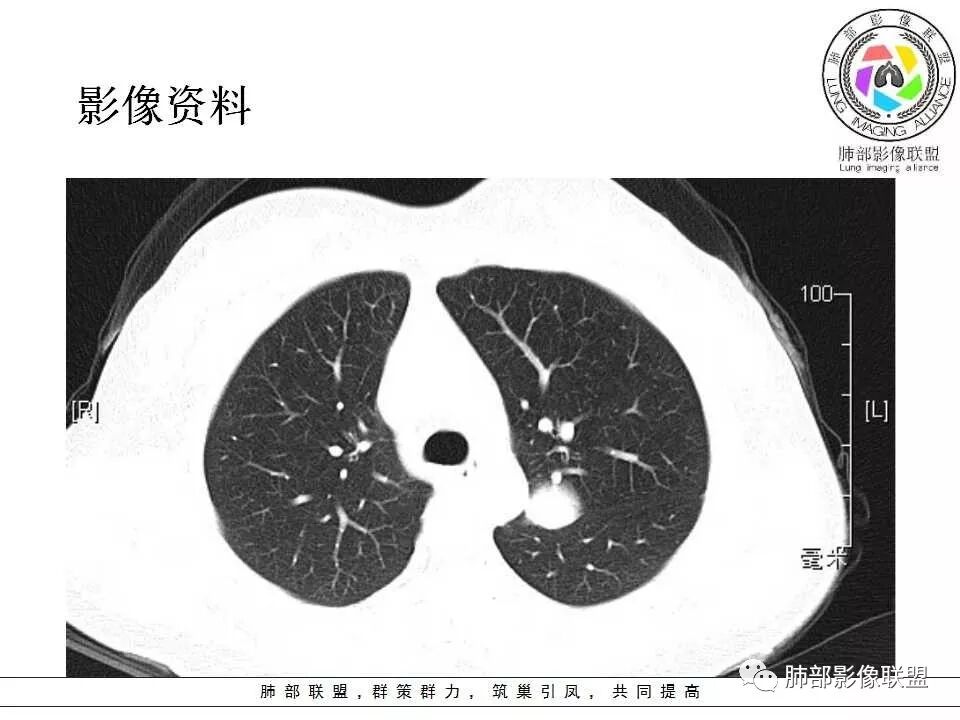

学习一下南大的诊断思路,左肺门区病灶,应该没跨叶,感觉都在上叶,强化密度均匀,边缘清晰,与支气管关系不大,常规考虑良性病变,PSP可能性大,鉴别CD,血管源性。但是一年增大怎么解释,不知道增大多少。

左肺病灶与支气管关系密切,类癌粘膜下生长,支气管略变窄,支气管外病变较大,符合冰山征表现,一年内有增长,考虑类癌,鉴别PSP,建议薄层重建。

我怎么又感觉跨叶间裂了,而且有胸膜尾征和可疑的指状突起,强化很明显,考虑SFT可能大,鉴别类癌和CD

左肺上叶后段紧贴斜裂结节影,支气管通畅,斜裂无移位,说明病灶来源斜裂可能,强化密度均匀,边缘清晰,考虑良性病变,PSP可能性大,鉴别CD。

患者中年女性,发现左肺上叶占位1年余入院,随访发现体积增大。胸部CT:左肺上叶尖后段近肺门及叶间裂实性类圆形结节,病灶边界清楚光滑,增强可见病灶明显均匀强化,其旁未见支气管堵塞。综合考虑良性病变,孤立性纤维瘤可能,鉴别巨大淋巴结增生症及硬化性肺细胞瘤。

青年女性,左肺门占位。定位:跨叶间裂,下叶邻近支气管推压,考虑肺外病变。影像表现:血管贴边,边缘光滑,强化均匀,考虑良性病变,PSP可能大,鉴别CD。

青年女性,一年前发现肺结节,复查有增大,未见近期片对比,定位:左肺上叶左肺门旁见实性类圆形结节,边界清晰光整,有部分分叶征,增强有均匀强化,与左上叶后段支气管关系不好判断,左上叶后段支气管未显示,堵塞?狭窄?需冠矢状面看看,定性:常规考虑良性或低度恶性肿瘤,典型的类癌或硬化性肺细胞瘤psp可能,神经源性或神经内分泌肿瘤、巨淋巴结增生症CD不除外,转移瘤、孤立性纤维瘤待排,建议HRCT或支气管镜检查。

年轻女性,左肺门区占位,斜裂推移未跨叶,类圆形,增强扫描明显强化,和支气管关系显示不是太清楚,感觉关系不是太密切,未见阻塞性炎症,一年后有长大,首先考虑PSP,鉴别类癌,SFT。

36岁女性,发现左肺占位1年,时有干咳。CT:左肺门(上叶尖后段?)类圆形结节,边界清,靠前边缘似有GG0,近肺门侧与血管密切接触,似有小凸起,增强见明显均匀强化,似有条片状影往肺门侧血管钻。图片有点少,病灶与支气管的关系看不清(目前的图片与支气管不密切)。随诊结节增大,整体考虑典型类癌可能性大,鉴别硬化性肺细胞瘤。